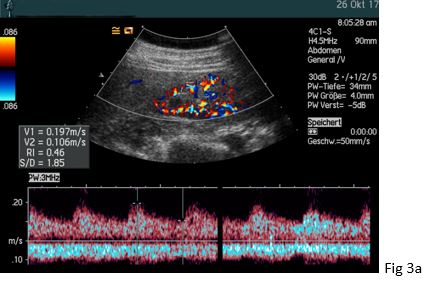

Figure 3: (a) The typical intrarenal interlobar poststenotic parvus-tardus spectrum is shown (RI 0.42 – 0.46) in comparison to the contralateral side (RI 0.62 - 65).

(b) The intrarenal interlobar spectrum one day after the successful percutaneous transluminal angioplasty showed normalisation of the resistive index (0.53, not shown).